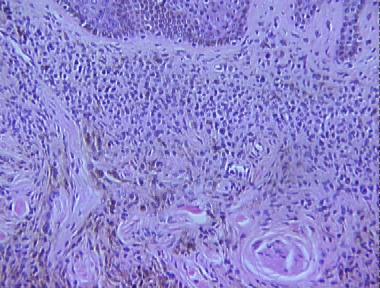

combined blue nevus

Histologic Features